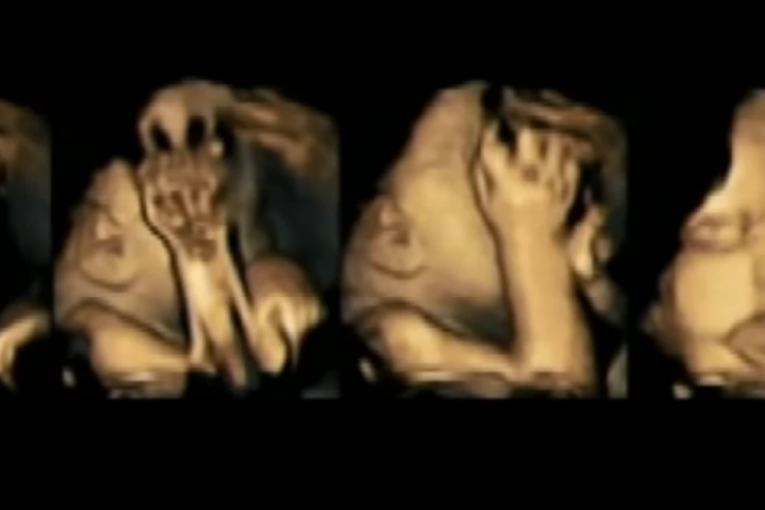

Na društvenim mrežama pojavio se ilustrovani snimak koji pokazuje kako se oseća beba dok majka konzumira cigarete. Može se primetiti da je vidno uznemirana i da deluje kao da se bori za vazduh.

Pogledajte snimak, pa razmislite još jednom kada ponovo krenete da zapalite cigaretu, a znate da u vašem stomaku raste novi život.